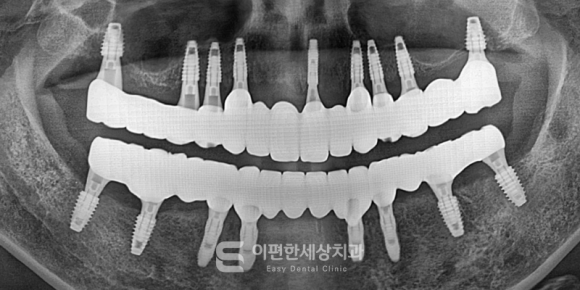

이해를 돕기 위한 전악임플란트 사진입니다.

위 참고 사진을 보았을 때,

전악 임플란트 치료, 쉽지 않아 보이죠.

몇 개의 치아를 심는 것과는 다릅니다.

거의 무치악 상태에서 여러 개의 임플란트를 식립해야 하고,

씹는 힘의 균형이나 교합, 심는 위치와 각도까지

전체적인 계획이 함께 고려되어야 하는데요.